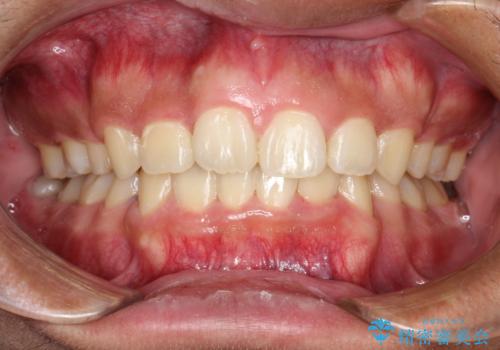

インビザラインを用いた非抜歯矯正